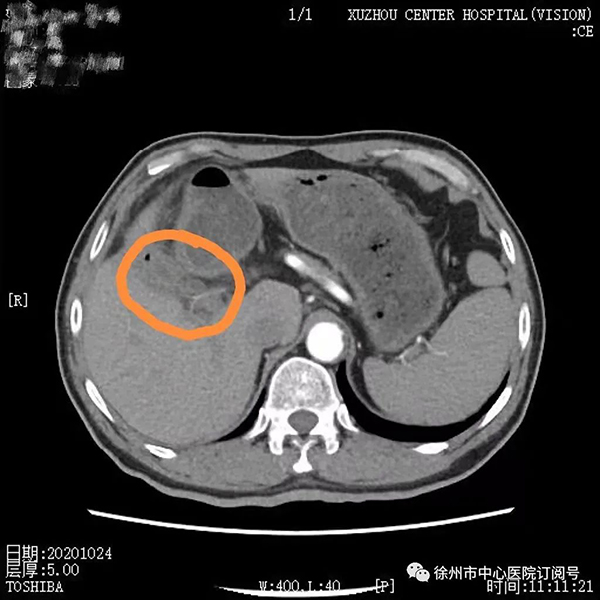

2020年8月,董先生行第一次靶免治療,無(wú)特殊不良反應(yīng),后間隔21天行一次治療至第4療程;2020年10月腹部CT檢查見(jiàn)腫瘤較前縮小,病情持續(xù)好轉(zhuǎn);2021年4月進(jìn)行第9療程再次復(fù)查腹部CT顯示,此時(shí)腫瘤較第一次治療時(shí)已明顯縮小。

2020年10月第4療程腹部增強(qiáng)CT:膽囊癌復(fù)查,鄰近肝臟斑片狀低密度較2020年8月明顯縮小、好轉(zhuǎn)。